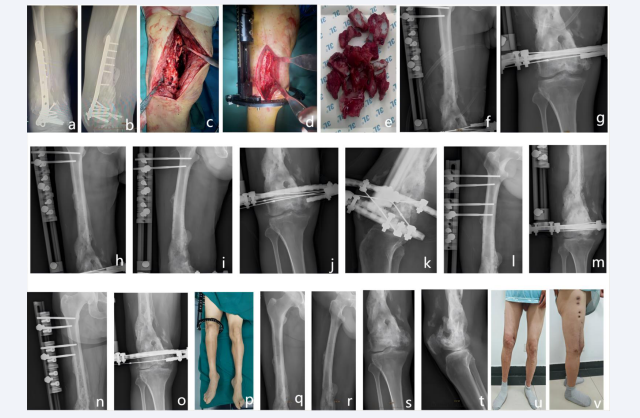

A total of 12 patients with post-traumatic osteomyelitis of the femur were identified as Cierny-Mader type IV, comprising 8 males and 4 females with a mean age of consultation of 40.08 years (ranging from 14 to 69 years). Four patients (33.33%) had additional medical conditions, including hypertension, type 2 diabetes mellitus, gentamicin allergy, penicillin allergy, and the location of the injury. Ten cases were located on the left side, and two were located on the right side. The causes of injury are as follows: Five cases were attributed to traffic accidents, four to falls from height, two to horseback riding, and one to being struck by a tree. The symptoms of morbidity were predominantly characterised by redness, swelling, pain, skin breakdown, and the formation of sinus tracts. In a few cases, these symptoms were accompanied by fever. Two cases manifested the symptoms of morbidity as vague pain and pain, respectively. The location of occurrence was the proximal one-third of the femur in three cases, the middle one-third of the femur in six cases, and the middle-distal one-third in two cases. In two cases, the proximal one-third of the femur was affected, while in one case, the distal one-third was affected. The majority of the abnormal serological indexes were CRP, ESR, WBC, and IL6. The 11 cases were treated with vancomycin-loaded calcium sulfate, while one case opted for vancomycin combined with gentamicin-loaded calcium sulfate implantation. Bacterial cultures of all 1 patient were diagnosed with methicillin-resistant Staphylococcus aureus (MRSA) infections. In one case, vancomycin was used to treat the infection, while cefazolin sodium was employed in three cases and cefuroxime sodium in six cases. Clindamycin was used in one patient who was allergic to cefazolin sodium and cefuroxime sodium, as well as in one instance of penicillin sodium for anti- infection purposes. The follow-up period spanned a duration of 31 to 49 months, with a mean follow-up time of 39.17 months. At the six-month postoperative follow-up, X-rays demonstrated a gradual resorption of the drug-carrying calcium sulfate, osteogenesis induced by the drug-carrying calcium sulfate in the area of the fracture and bone defects, localized scab formation, and gradual The restoration of bone continuity was evident at the final follow-up, as demonstrated by the X-ray, which showed blurred boundaries of the plastinated loaded calcium sulfate, mature osteoinduction and bone remodeling, restoration of both osteocortical continuity, and a patent medullary cavity. Typical case pictures are shown in Figure 2.

Figure 2 Patient, male, 58 years old, presented with osteomyelitis of the left femur after a traffic accident. a-b Pre-operative X-rays showed that the left femur was internally fixed and infected. c-e Intra-operative removal of the internal fixation and removal of the dead bone. f-g X-rays one day after implantation of external fixation bracket combined with drug-carrying calcium sulphate showed that the drug-carrying calcium sulphate was anastomosed with the bone defect site. h-k, i-m X-rays at 6 months after surgery showed that the drug-carrying calcium sulphate was gradually absorbed and the external fixation bracket was stabilised. X-rays at 6 months after h-k and i-m showed that the drug-loaded calcium sulphate in the bone defect was gradually absorbed and the external fixation bracket was stable; n-p X-rays at 10 months after the operation showed that the bone defect had healed well and it was proposed to remove the external fixation bracket. q-v X-rays at 24 months after the operation showed that the bone defect had healed well, and the affected limb was fully loaded and could maintain basic daily life, even though there was stiffness in the joints.

Figure 2: Patient, male, 58 years old, presented with osteomyelitis of the left femur after a traffic accident. a-b Pre-operative X-rays showed that the left femur was internally fixed and infected. c-e Intra-operative removal of the internal fixation and removal of the dead bone. f-g X-rays one day after implantation of external fixation bracket combined with drug-carrying calcium sulphate showed that the drug-carrying calcium sulphate was anastomosed with the bone defect site. h-k, i-m X-rays at 6 months after surgery showed that the drug-carrying calcium sulphate was gradually absorbed and the external fixation bracket was stabilised. X-rays at 6 months after h-k and i-m showed that the drug-loaded calcium sulphate in the bone defect was gradually absorbed and the external fixation bracket was stable; n-p X-rays at 10 months after the operation showed that the bone defect had healed well and it was proposed to remove the external fixation bracket. q-v X-rays at 24 months after the operation showed that the bone defect had healed well, and the affected limb was fully loaded and could maintain basic daily life, even though there was stiffness in the joints.